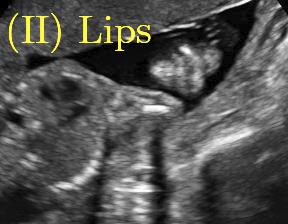

Row I in Fig. 6 shows a fetal brain image from . The confidence estimation of shadow regions from the baseline, the proposed method and the proposedAG method are similarly accurate since we use fetal brain images to train the confidence estimation networks in these three methods. These outperform [16] and [22]. Rows (II-IV) in Fig. 6 show shadow confidence maps of non-brain anatomy from , including lips, abdominal and cardiac. The baseline failed on unseen data during inference. However, the proposed methods are able to generate accurate shadow confidence maps because of the generalized shadow features obtained by the shadow-seg module. Furthermore, the “Lips” example shows that our method is capable of detecting weaker shadow regions that have not been annotated in manual segmentation. This indicates that the confidence estimation network has learned general properties of shadow regions.